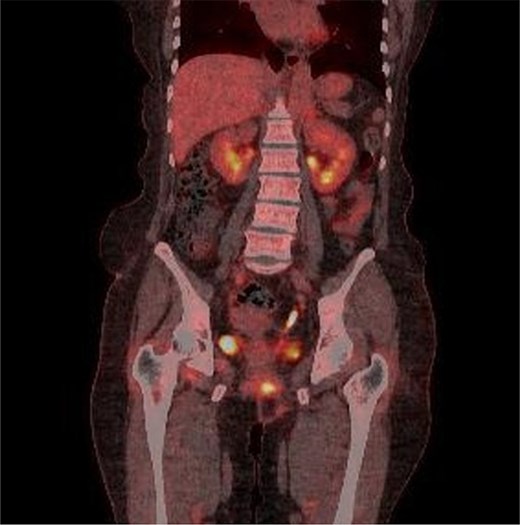

Multiple intense hypermetabolic mass lesions identified from the anus to the rectum, accompanied by numerous hypermetabolic lymph nodes in the pelvis.